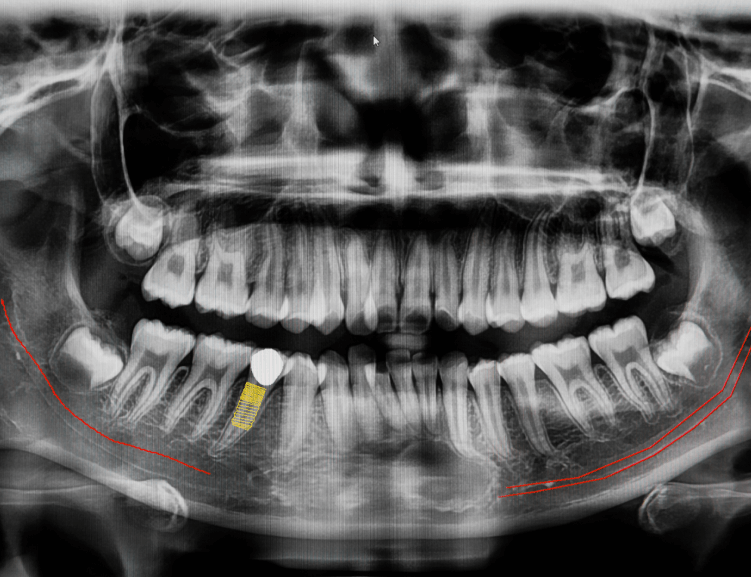

Çene ameliyatı, diğer adıyla ortognatik cerrahi, çene kemiklerinin düzensizliklerini düzeltmek ve hizalamayı iyileştirmek için uygulanan bir prosedürdür. Bu tedavi, yalnızca işlevi değil, aynı zamanda yüz görünümünü de iyileştirir.

Diva Diş Kliniği'nde uzmanlık ve son teknoloji cihazları bir araya getirerek ihtiyaçlarınıza uygun mükemmel sonuçlar sunuyoruz.